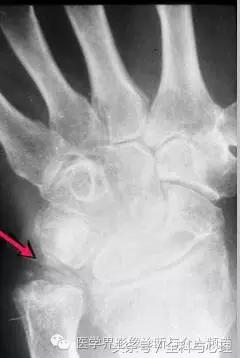

四、软骨来源的钙化:

常见于膝盖、耻骨联合、臀部、尺骨三角纤维软骨复合体、肩关节。

软组织钙化与骨化,软组织钙化和骨质增生 尺骨三角纤维软骨复合体钙化